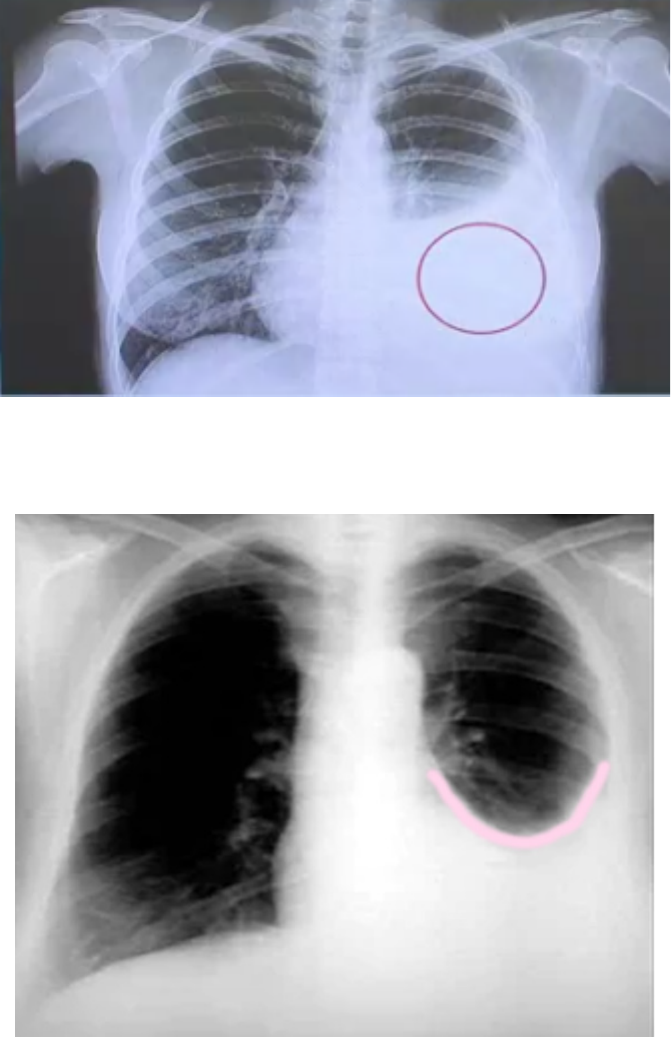

à Raio-X de Tórax Posteroanterior com líquido pleural detectável entre 100 a 150 mL

Parábola de Damoiseau:

Antes e depois da Toracocentese:

Expansão pulmonar após toracocentese.